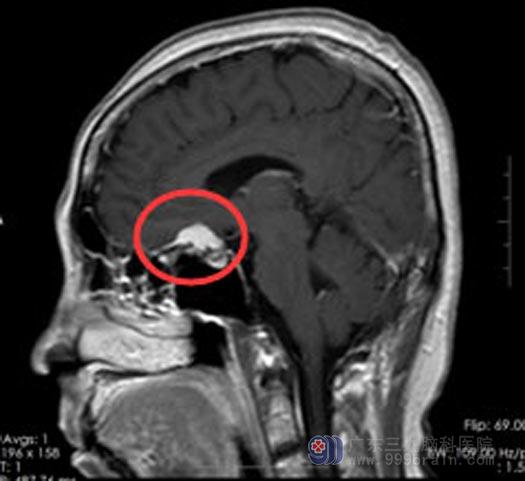

61岁陈阿姨,两年前开始看不清东西,左眼比右眼严重。配了老花镜,但是并不管用,当时的视力只能勉强满足基本生活需求。近两个月以来,视物模糊的症状变得越来越严重,看报纸都变得吃力,同时还伴有头晕头痛症状。家人陪着她在当地医院就诊,诊断为“鞍区占位,考虑脑膜瘤”。

入住广东三九脑科医院综合神经外科后,立即紧锣密鼓地准备手术,这是和时间在赛跑,因为只要双眼视力完全丧失,那就再无回天之力。由鲁明主任主刀行“鞍结节脑膜瘤切除术”,术中见肿瘤已经将左侧视神经压扁,庆幸的是,手术很顺利,肿瘤完全切除,双侧视神经得到了充分的减压。术后,陈阿姨的视力有了明显改善,头痛头晕症状也得到缓解。

手术前